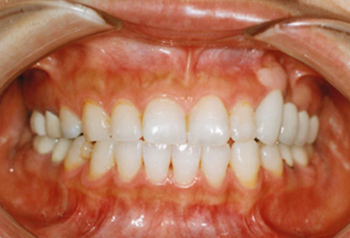

主訴:上顎左側3番を残して欲しい

診断名:上顎左側3番歯肉カリエスにより挺出を行い、上顎左側③4⑤⑥番ブリッジを装着

症状:歯ぎしりがある

患者プロフィール:北九州市小倉北区30代女性

治療方針:上顎左側3番歯肉縁下カリエスにより挺出を行い、上顎左側③4⑤⑥番ブリッジを装着する

治療装置:白い表側矯正装置(マルチブラケット)

抜歯:非抜歯

治療期間:約6か月

説明したリスク副作用:痛み・治療後の後戻り・歯根吸収・歯髄壊死など